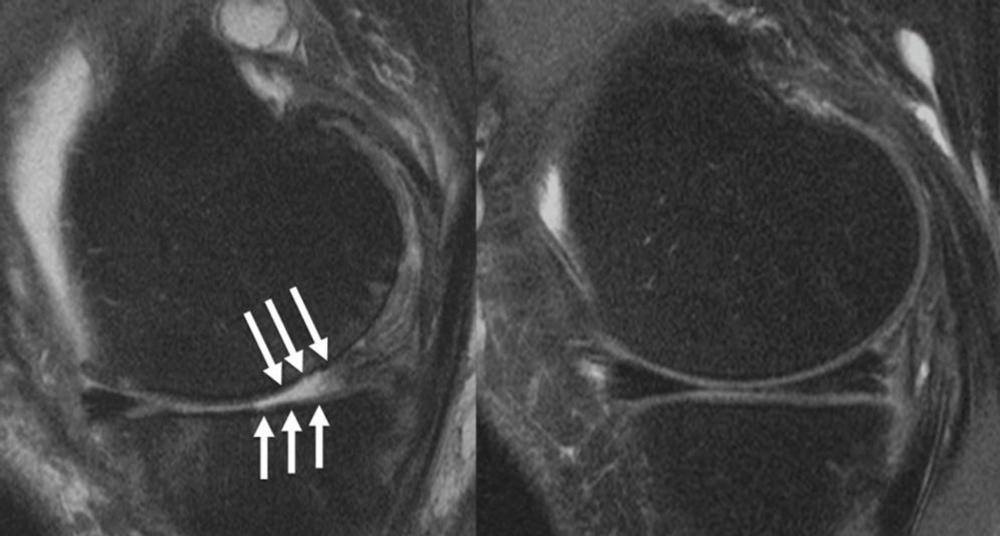

Figure 1. Knee joint of a patient showing (A) severe cartilage defects and (B) intact knee joint.